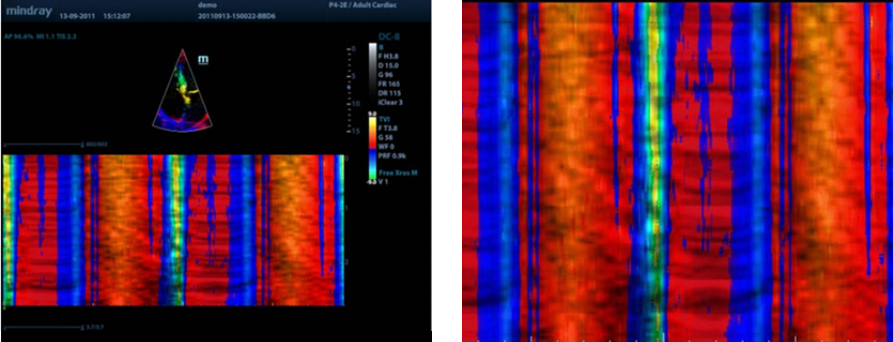

Free Xros M?

Observa??o anat?mica precisa com a coloca??o livre de linhas de amostra em qualquer ?ngulo. Melhores imagens por meio da exibi??o simult?nea de at├® 3 linhas de amostra.